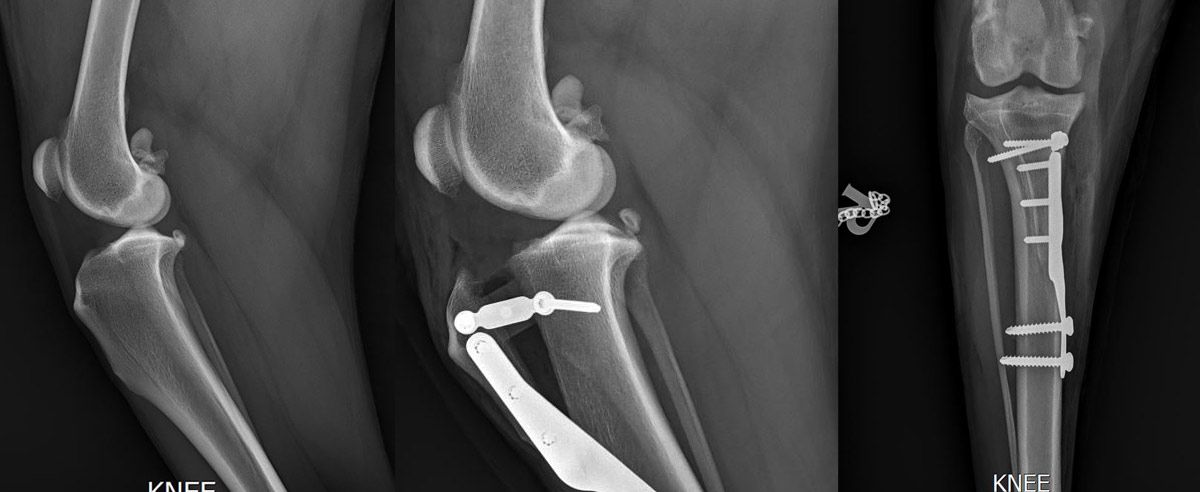

- Bildgebende Verfahren

• Röntgenaufnahmen